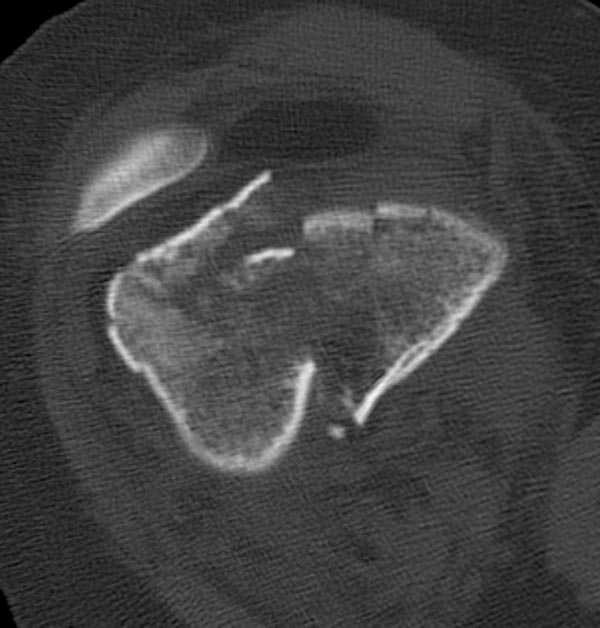

[Ortho] Дистальный перелом бедра

Бесспорно, предлагаемый ретроградный метод имеет свои преимущества, но имеется опасность при манипуляции интрамедуллярным гвоздем расколоть мыщелки.

Раскол можно предупредить шурупами, но короткий дистальный фрагмент навряд ли позволит добиться адекватной стабильности конструкции. Стандартные гвозди не рассчитаны для таких переломов, и если все таки желаете провести фиксацию гвоздем, тогда надо заказывать специальный custom made nail т.е. с расширенной возможностью дистальной блокировки.

Поэтому такие меж и над- мыщелковые переломы более предпочтительным считается фиксировать мыщелковыми пластинами